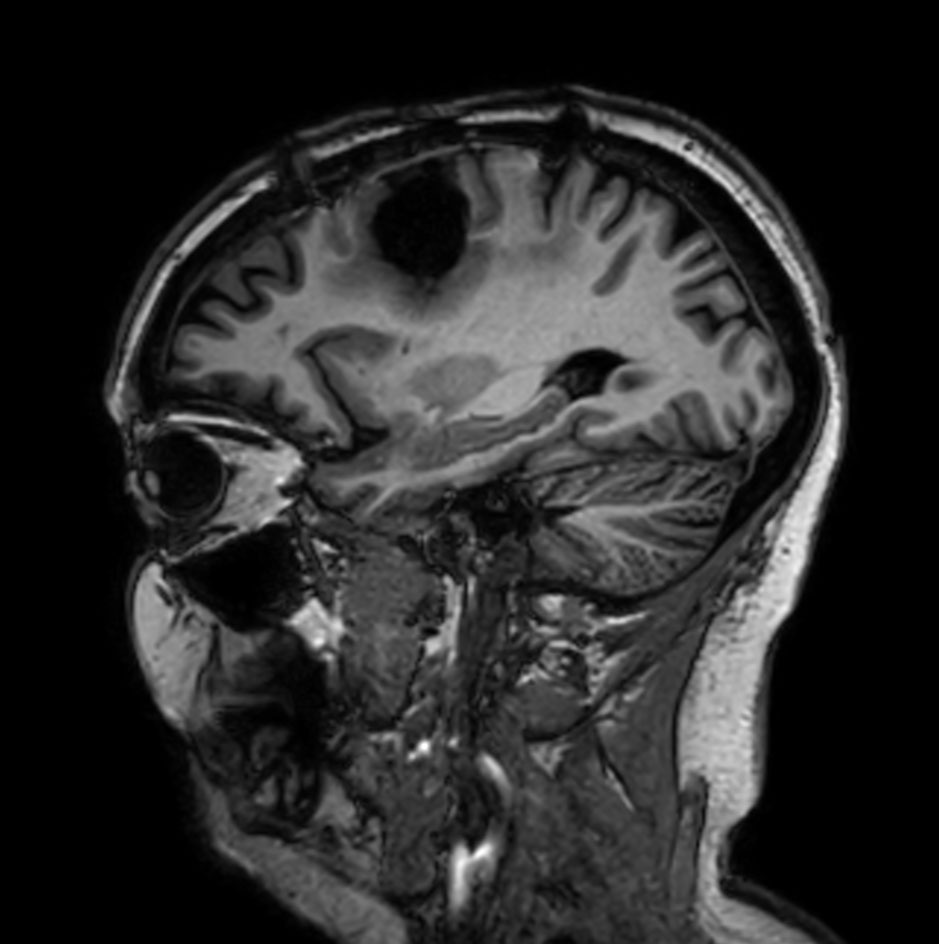

Sagittal 3D T1w TFE